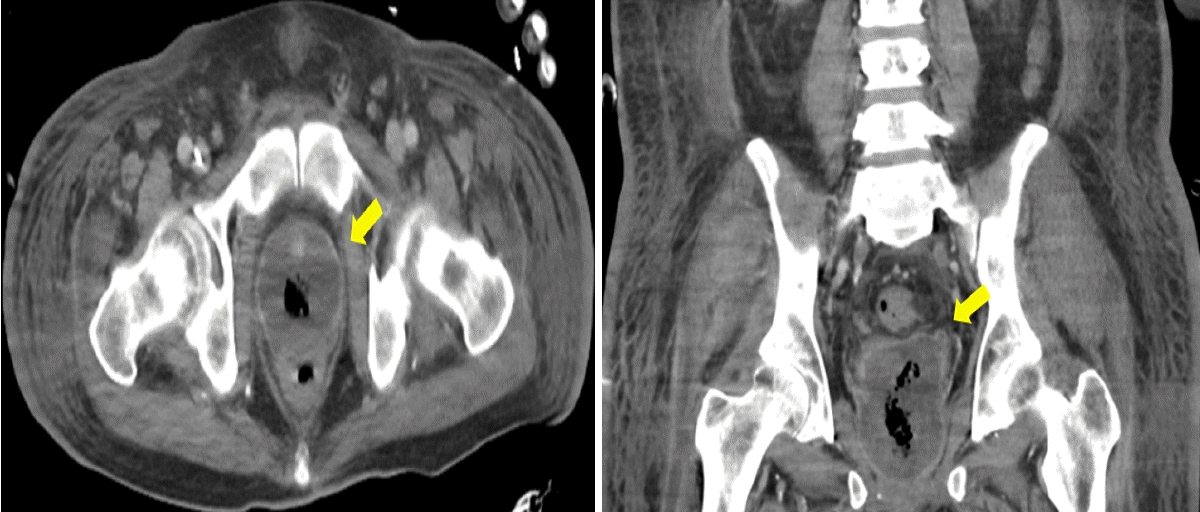

After his transfer to the general ward, he experienced recurrent fevers with elevated inflammatory markers, suggesting that the prostate infection with the abscess was not fully controlled. Consequently, the patient underwent transurethral drainage of the prostate abscess 1 month after admission. He gradually recovered post-surgery and received targeted parenteral antibiotics for 12 weeks based on the pathogens isolated from the initial blood cultures. He was discharged from the hospital with a cystostomy tube in place after discontinuing antibiotics and having no fever for 2 weeks. Subsequent abdominal CT scans showed a reduction in the size of the prostate abscess (Dmax, 5.4 cm). Thereafter the cystostomy tube was changed monthly due to the risk of urinary retention, as indicated by cystography showing a completely obstructed urethra (Fig. 4).

Figure 4.

Follow-up cystography after hospital discharge reveals a completely obstructed urethra (arrow), necessitating the maintenance of the patient’s cystostomy.